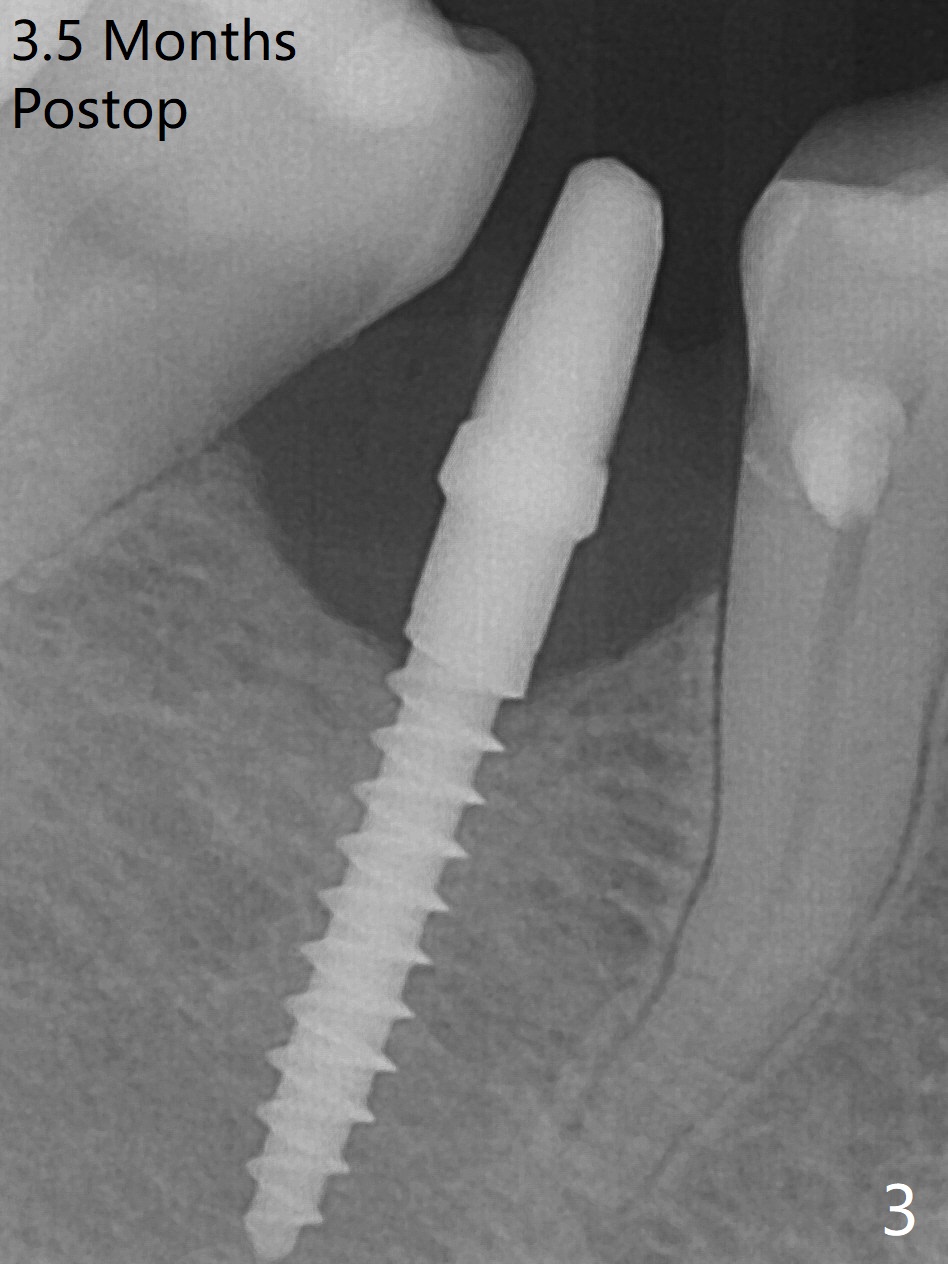

The mesial surface of the tooth #31 is reduced prior to osteotomy (Fig.1 >) so that the mesiodistal width of the edentulous area is 4.5 mm. An incision is made instead of tissue punch because of the narrow keratinized gingiva. The potential osteotomy site happens to have nonkeratinized tissue. When a 2.5x12(2) mm 1-piece implant is placed, it is close to the curved root of the 2nd premolar (Fig.2 *). Because of apparently sufficient clearance from the Inferior Alveolar Canal (Fig.2 red dashed line), the implant is placed ~ 1 mm deeper later. After suturing, periodontal dressing is applied. At patient's request, a provisional is fabricated with occlusal clearance 26 days postop. The occlusal surface of the provisional perforates 3.5 months postop with the provisional having pressed the gingiva, which is consistent with crestal bone loss (Fig.3). There appears no bone loss 3 months post cementation (Fig.4). There is minimal bone loss 11 months post cementation; in fact the bone density around the coronal portion of the implant increases (Fig.5).